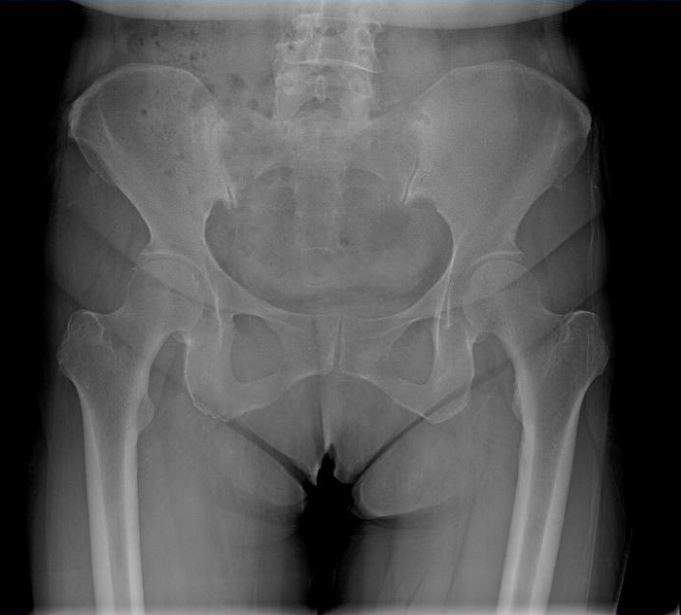

女 65岁

左侧膝关节置换术后

左侧膝关节置换术后复查

通过全景拼接图像可以清晰显示双下肢对比情况,为术后评估提供更多影像学资料。